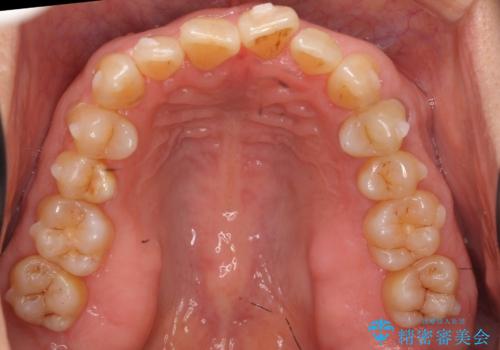

右下の犬歯の1本抜歯で最小限の抜歯で並べることができました。

奥歯も上下交互になるようにかみ合わせることができました。